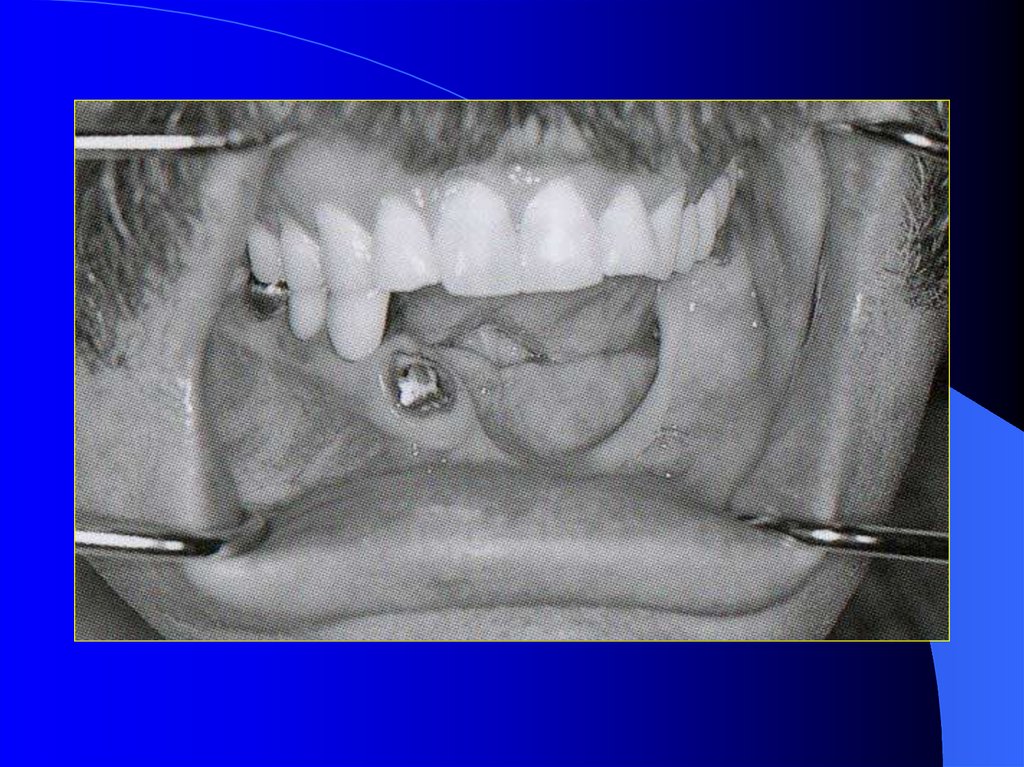

31. Alt çene devamlılığı olmayan dişsiz hastalar

Tedavisi en zor olan vakalardır. Klinikte

sıklıkla rastlanmaktadır.

Dil, yanaklar, çevre dokular protezin cilalı

yüzeyleriyle ve dişleri ile uyum sağladığı

ölçüde stabilte artar.

Skatris dokuları ve cerrahi işlem yapılan

bölgedeki hissizlik protezi olumsuz etkiler.